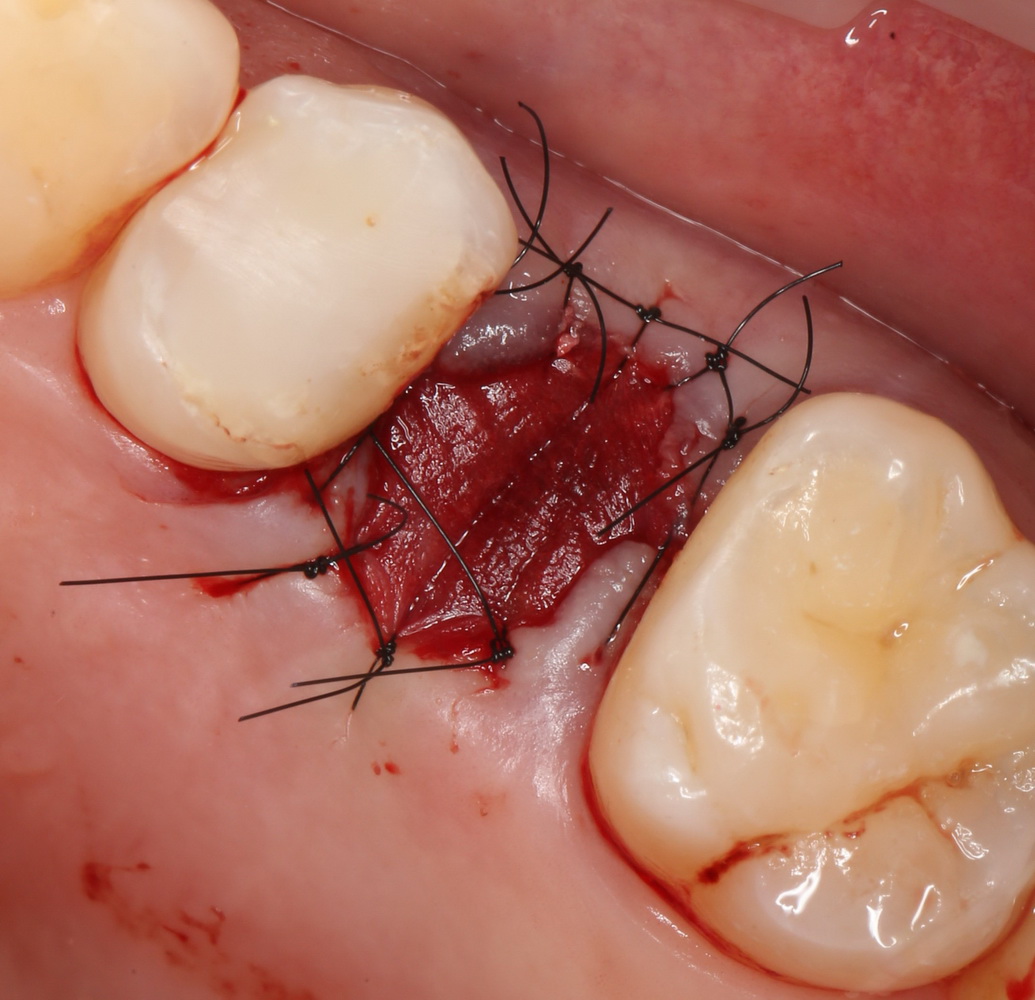

Итак, мы удаляем клык, по шаблону устанавливаем импланты, строим «каркас» будущего альвеолярного гребня в области пятерки:

Для синуслифтинга мы используем Geistlich Bio-Oss, который пригодился нам как для остеопластики (наполнения построенного «каркаса»), так и для аугментации лунки:

Проводя остеопластику, мы не забываем о «факторах успеха остеопластических операций«, в частности о факторе #3. Поэтому, несмотря на то, что «классикой» немедленной имплантации является установка формирователя десны, мы перекрываем лунку клыка барьерной мембраной и ушиваем ее наглухо: